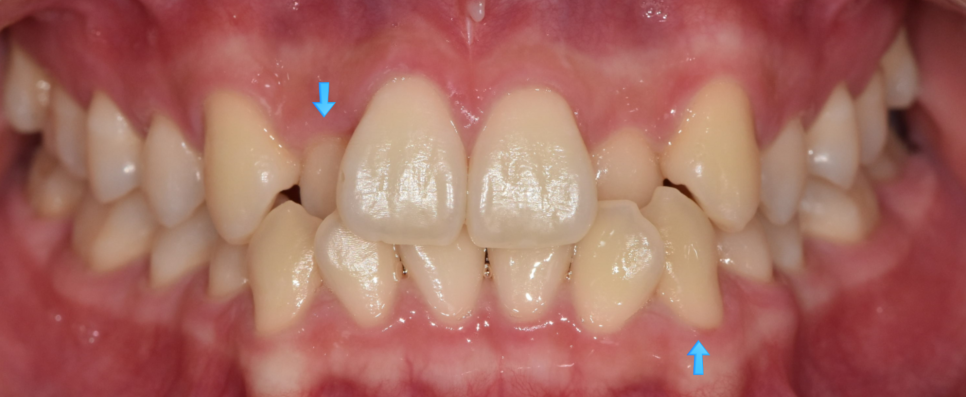

사진처럼 다른 치아에 비하여 안쪽으로 들어가 있기도 하고

튀어 나와있는 경우도 있지만

치아 배열이 울퉁불퉁한 것이라 보시면 됩니다.

250616 양치가 어렵겠죠?

들어가 있는 치아와 나와있는 치아

불규칙한 치아 배열로 칫솔질이 어렵고

양치가 잘 안되는 사각지대가 생길 수 있겠죠??